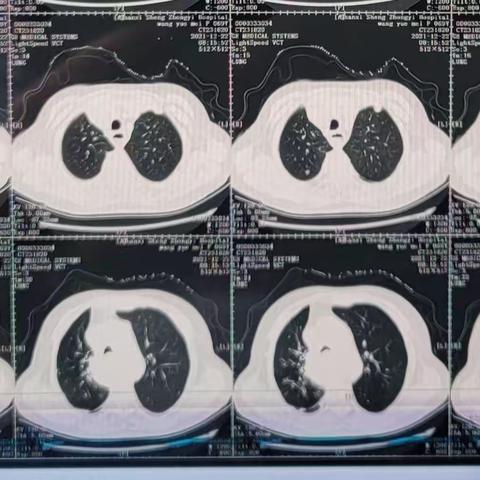

主动脉弓旁小细胞肺癌粒子植入术后纵隔血肿